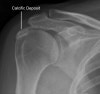

X-ray는 석회성 건염의 진단에 가장 중요한 검사입니다.

대개 AP view에서 견봉하 공간의 대결절 바로 위, 즉 극상건 종지부 근처에 타원형 모양의 방사선 비투과성 음영이 관찰됩니다.

침착은 다양한 모양과 크기로 나타날 수 있으며, 극상선 이외의 다른 건에 발생한 경우에는 내회전 영상이나 액와 촬영에서 잘 관찰되기도 합니다(어떤 경우 뼈에 가려 잘 보이지 않으며, 촬영 시 통증 때문에 팔을 돌리지 못해서 가려지기도 하며, 석회화가 아주 작아 잘 보이지 않기도 합니다).

Acute : Loss of angular contour, Decreased density, Eventual blurring

Chronic : Dense angular calcification

X-ray : 석회화 건염(Calcific tendinitis, Calcific tendonitis)